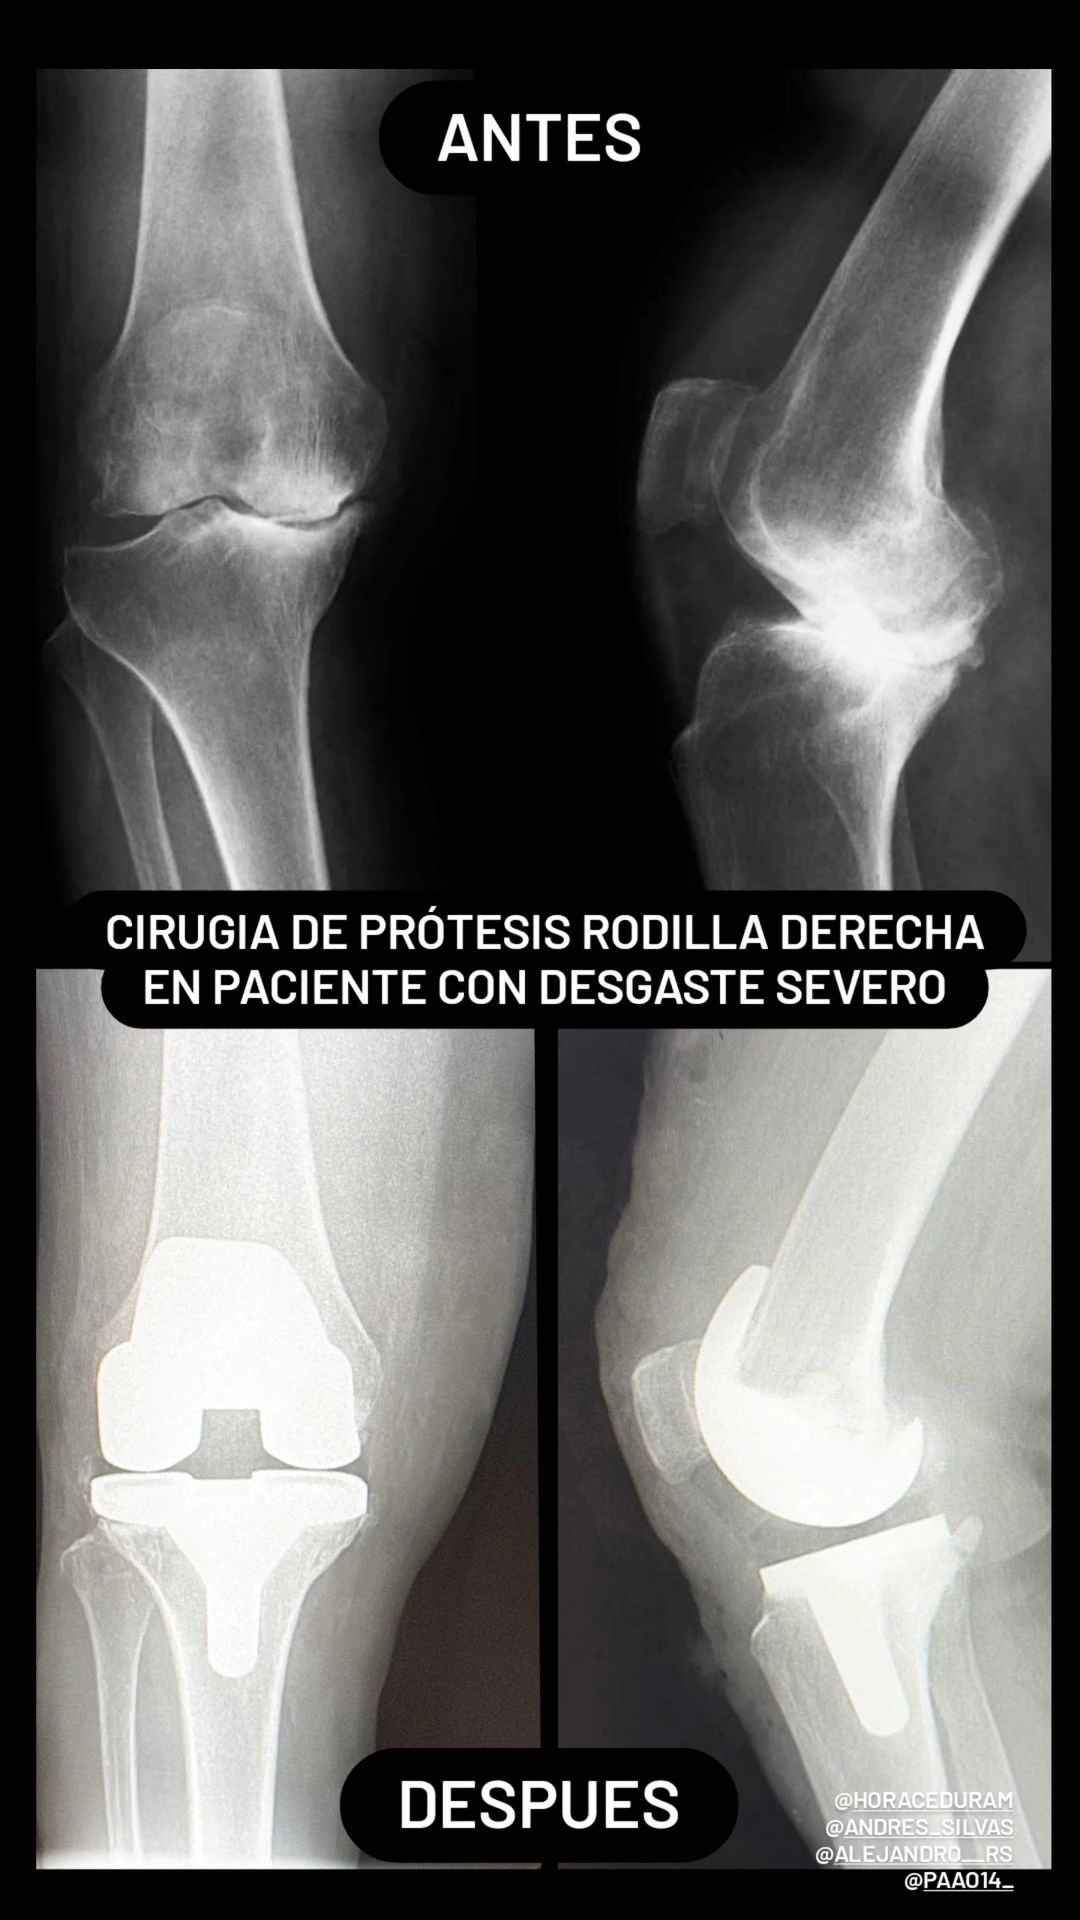

• Prótesis de Rodilla

• Desgaste de rodilla

Artroplastia rodilla con prótesis total Sin especificar